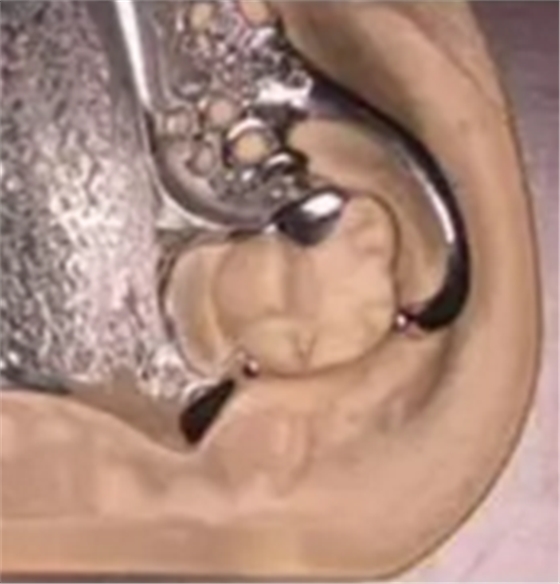

(四)近中合支托鑄造三臂卡環(huán)(也有稱之為G型卡環(huán)或改良RPA)

(引自A.Shifman,Z.Ben-Ur)

(圖14)

(圖14-15,總義齒與可摘局部義齒的設(shè)計)

組成:遠(yuǎn)中鄰面板、鑄造近中合支托、舌側(cè)鑄造對抗臂、頰側(cè)鑄造Aker固位臂(當(dāng)然也可用其他圓環(huán)形卡環(huán),根據(jù)觀測類型還可用I桿、L卡、T卡等桿式卡環(huán))。與傳統(tǒng)鑄造遠(yuǎn)中合支托三臂卡環(huán)相比,其結(jié)構(gòu)看似只是合支托位置的前移,其實不然:①遠(yuǎn)中鄰面板、頰側(cè)的Aker固位臂制作要求與RPA卡環(huán)完全一樣,即不能妨礙鞍基的自由下沉;②對抗臂要粗一些、更堅固一些,最關(guān)鍵的是,同遠(yuǎn)中鄰面一樣,舌側(cè)需要制備導(dǎo)平面尤其舌側(cè)用舌面板時(圖17)。沒有舌側(cè)導(dǎo)平面,它什么都不是。主要用于下頜前磨牙。優(yōu)點:減少小連接體的數(shù)目,增加舒適感。